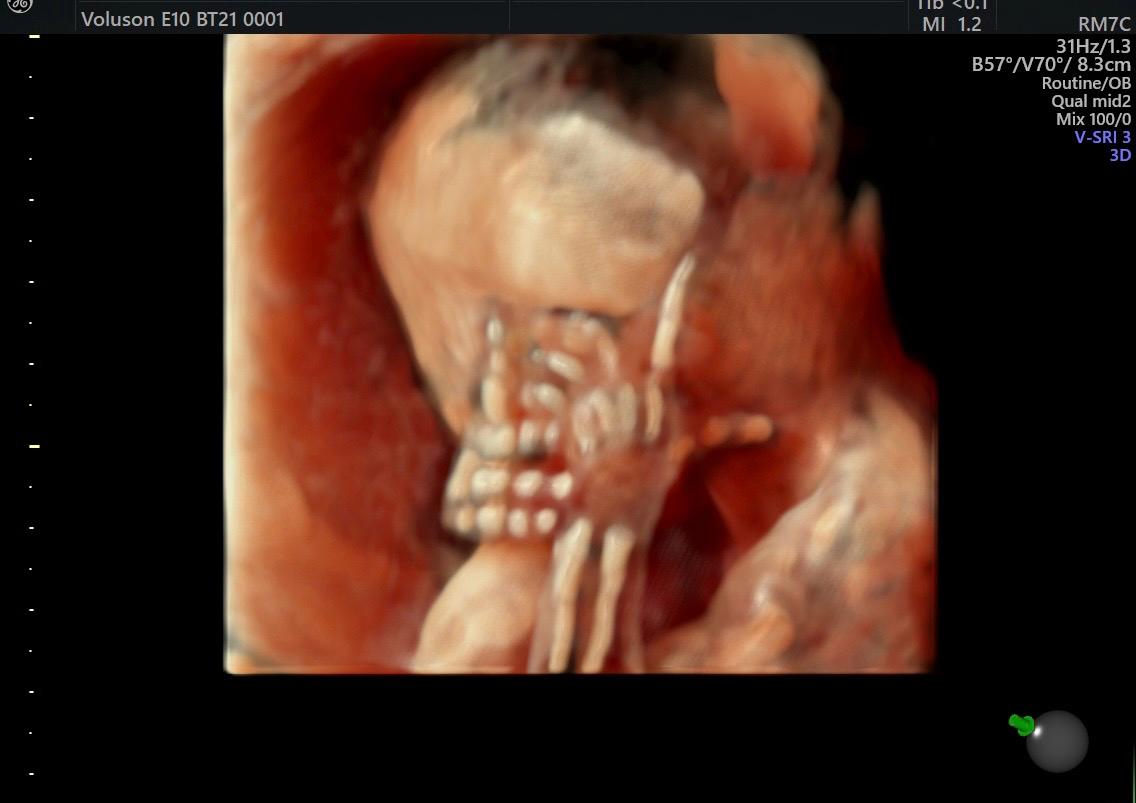

Fetal Medicine

Ultra Sound

Gallery

Images

Photos